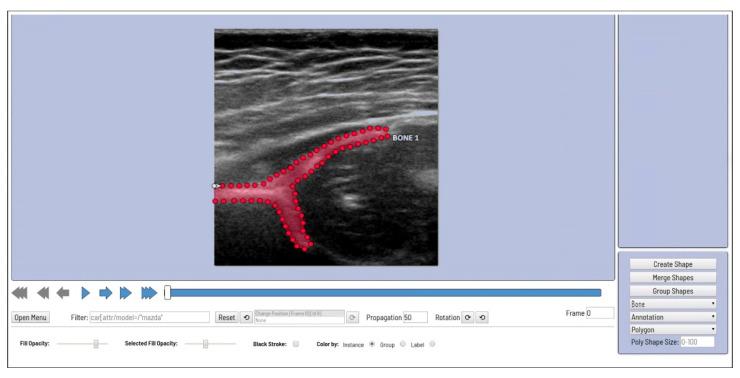

Hip joint ultrasonographic (US) imaging is the golden standard for developmental dysplasia of the hip (DDH) screening. However, the effectiveness of this technique is subject to interoperator and intraobserver variability. Thus, a multi-detection deep learning artificial intelligence (AI)-based computer-aided diagnosis (CAD) system was developed and evaluated. The deep learning model used a two-stage training process to segment the four key anatomical structures and extract their respective key points. In addition, the check angle of the ilium body balancing level was set to evaluate the system's cognitive ability. Hence, only images with visible key anatomical points and a check angle within ±5° were used in the analysis. Of the original 921 images, 320 (34.7%) were deemed appropriate for screening by both the system and human observer. Moderate agreement (80.9%) was seen in the check angles of the appropriate group (Cohen's κ = 0.525). Similarly, there was excellent agreement in the intraclass correlation coefficient (ICC) value between the measurers of the alpha angle (ICC = 0.764) and a good agreement in beta angle (ICC = 0.743). The developed system performed similarly to experienced medical experts; thus, it could further aid the effectiveness and speed of DDH diagnosis.

髋关节超声(US)成像术是发育性髋关节发育不良(DDH)筛查的金标准。然而,该技术的有效性受到操作者间和观察者内变异性的影响。因此,开发并评估了一种基于多检测深度学习人工智能(AI)的计算机辅助诊断(CAD)系统。深度学习模型采用两阶段训练过程来分割四个关键解剖结构并提取其各自的关键点。此外,设置了髂骨体平衡水平的检查角度以评估该系统的认知能力。因此,分析中仅使用具有可见关键解剖点且检查角度在±5°以内的图像。在原始的921张图像中,有320张(34.7%)被系统和人类观察者均认为适合筛查。在合适组的检查角度方面观察到中度一致性(80.9%)(Cohen's κ = 0.525)。同样,在α角测量者之间的组内相关系数(ICC)值方面存在高度一致性(ICC = 0.764),在β角方面存在良好一致性(ICC = 0.743)。所开发的系统表现与经验丰富的医学专家相似;因此,它可以进一步提高DDH诊断的有效性和速度。